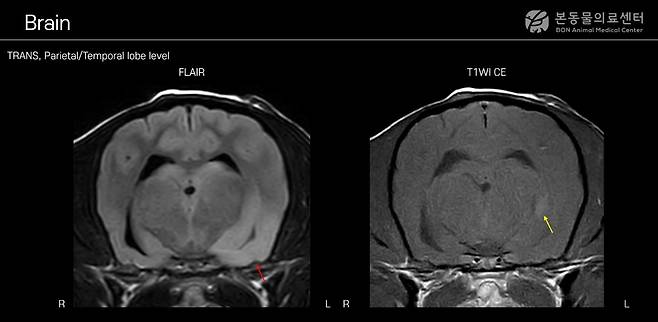

최근 본동물의료센터에는 안면부 부분 발작과 보행실조 증상을 보인 8살령 중성화 수컷 포메라니안이 내원했다. 신경학적 검사에서 병변이 뇌에 국한된 것으로 판단돼 MRI 검사를 실시했다. 그 결과 좌측 대뇌 반구에 광범위한 염증성 병변이 확인됐다.

이어 시행한 뇌척수액 검사에서는 총 유핵세포수 증가와 단핵세포 우세 소견이 확인됐다. 감염성 질환 배제 검사를 종합한 결과 MUE로 잠정 진단됐다.